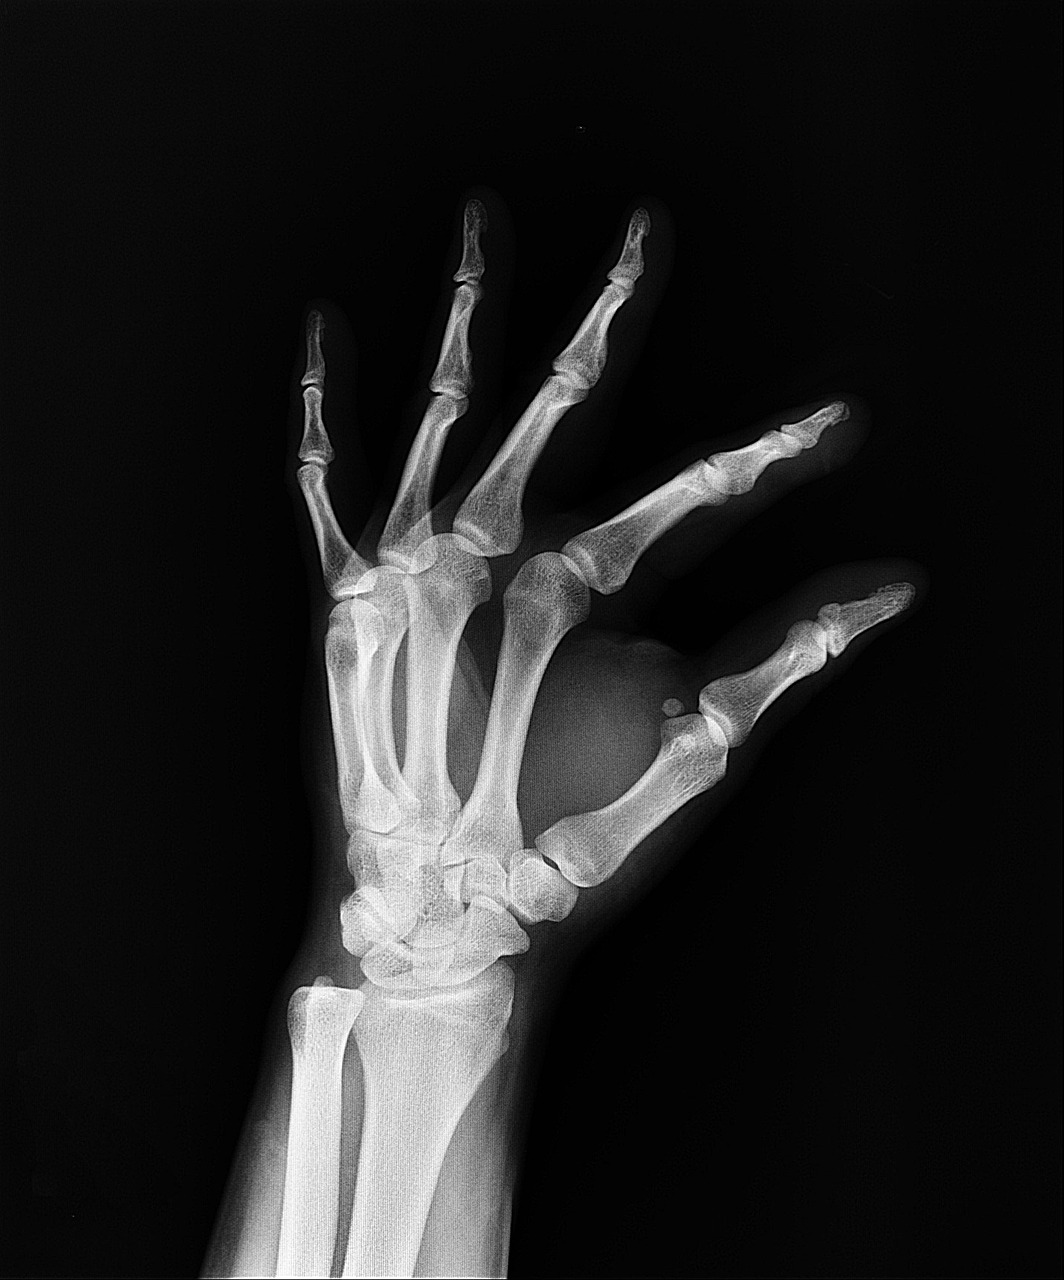

물리치료는 디스크, 염좌, 근육통, 오십견 등 다양한 근골격계 질환에 필수적인 치료법입니다. 꾸준히 치료받아야 효과를 볼 수 있지만, 병원비 부담 때문에 망설이는 경우가 많죠. 이럴 때 실손보험은 매우 큰 도움이 됩니다.